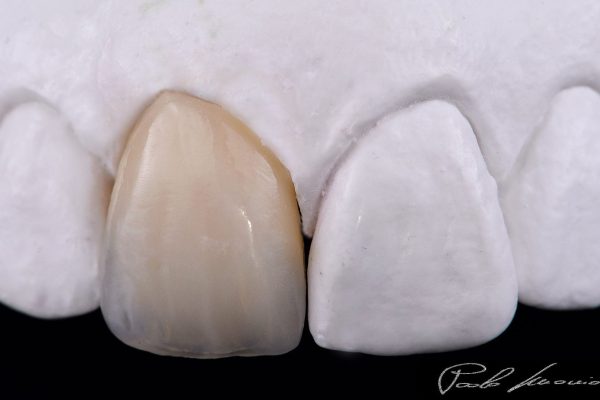

The BioCeramiche, realized by us, are protected in their recipe and manufacturing process by THREE INTERNATIONAL PATTENTS of our exclusive property (n° 01315293 – 01307082 – 01343575 Submitted to the Ufficio Italiano Brevetti) .

We are therefore able to create Unique, Personalized, and Original products